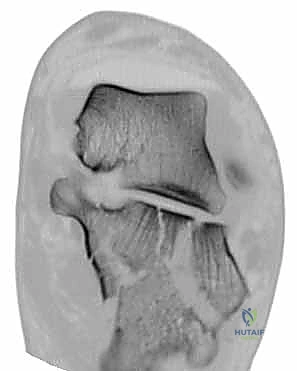

- الأشعة المقطعية (CT Scan): وهي الخطوة الأهم والأكثر حيوية. توفر الأشعة المقطعية صوراً ثلاثية الأبعاد وتقاطعاً دقيقاً للكسر، مما يسمح بتصنيف الكسر (نظام ساندرز - Sanders Classification) وتحديد عدد الشظايا العظمية ومدى انزياحها داخل المفصل. بناءً على هذه الأشعة، يضع الدكتور هطيف خطته الجراحية الدقيقة.

3. كشف الكسر وإعادة البناء (Reduction)

بمجرد كشف العظم، يتم تنظيف التجمع الدموي. يقوم الجراح بكشف السطح المفصلي المكسور. باستخدام أدوات دقيقة، يتم رفع الشظايا العظمية المنخسفة إلى مكانها التشريحي الأصلي. يتم استعادة ارتفاع وعرض العظم، والأهم من ذلك، استعادة السلاسة التامة لسطح المفصل.

صور إضافية من داخل غرفة العمليات توضح دقة الإجراء

توضح الصور التالية مدى تعقيد الجراحة والدقة التي يتطلبها تثبيت عظم الكعب، والتي يعكسها التميز الجراحي للأستاذ الدكتور محمد هطيف: